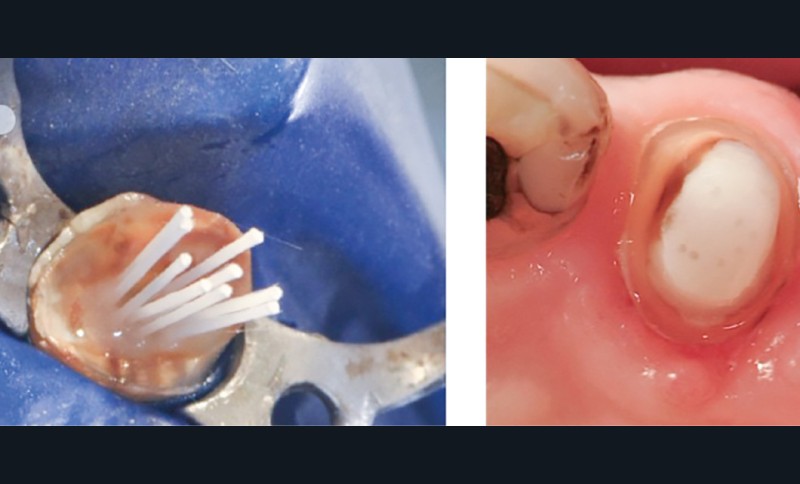

Le concept de la RMIPP a vu son indication élargie par l’amélioration des systèmes de collage. Les adhésifs universels en deux flacons présentent aujourd’hui des valeurs d’adhésion jusqu’à deux fois supérieures aux adhésifs monoflacon, permettant ainsi d’éviter les ancrages radiculaires. L’exploitation des contre-dépouilles apportée par la préservation des structures dentaires permet d’augmenter la macro rétention des résines composites. Lorsque l’ancrage radiculaire est nécessaire, les études in vitro révèlent que l’utilisation de micro tenons fasciculés (multi-tenons fibrés) augmente d’autant plus la résistance à la fracture par rapport aux tenons fibrés conventionnels [7] (fig. 4). L’aptitude au collage diminuant en direction corono-apicale par diminution du nombre de tubuli dentinaires, une longueur de préparation intra-canalaire de 5 à 6 mm sera considérée comme suffisante [8].